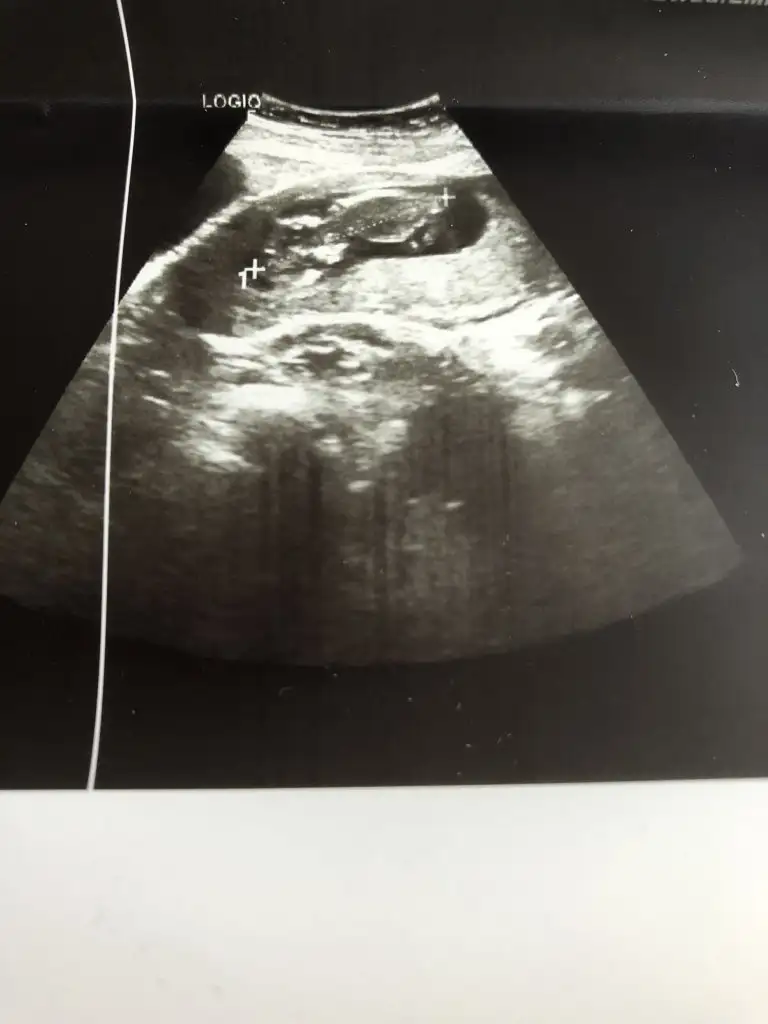

Benimkini de tahmin edebilirsinizErkek ve kız için 11 + 12+ yada 13 hafta usg görüntüsü olmalı açıklamalar asagıda yazıyorrabbim herkesin gönlüne göre nasip etsin inşallah .. ecmain

[/B]Eki Görüntüle 473828 gordugunuz gibi ust taraftaki simgedende anlasildigi gibi eger cikinti paralel ise kiz

yok 30°lik bir aciyla yukari dogru bakiyorsa %99 oglunuz olacak demektir simdi bi kac ornek resimler daha koyacagim kiziminkide dahil

Eki Görüntüle 473829 bu bir erkek bebek genital nub cikintisi gayet yukarda

Eki Görüntüle 473831 simdi burada cikintilara bakin eger bel popo cizgisine paralel ise kiz

yok 30 derecelik bir aciyla yukari bakiyorsa erkek

Hiç belli degilki detaylıda kız dedilerse kızdır cnm benim detaylıda ikisi kız dendi başka Dr 30 haftasında biri erkek dedi ama ikiz kızlarım doğduIkra meyra kız beklerken 28 haftada başka bi doktor erkek dedi sen bu görüntüde bişey görebiliyormusun

Bu net kız canimIkra meyra 16 haftalık bacak altından sence hangisine yatkın